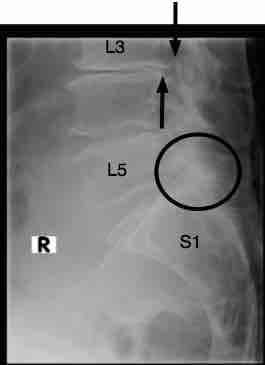

Did your xray look something like this?

After several months of chiropractic care and then physical therapy and epidural injections I had an MRI. Result was a severely "extruded" disc at L5-S1. So a few weeks later I had a bi-lateral microdiscectomy and laminectomy. Surgeon says surgery went great, but there was more "stuff" that had to be done than he expected.